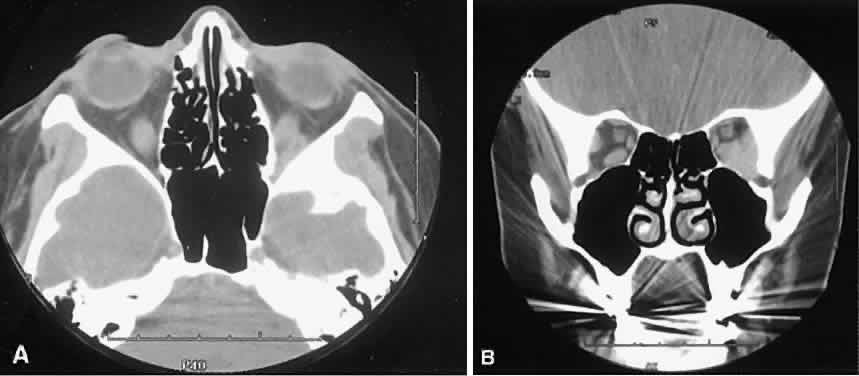

Graves' orbitopathy probably represents the most frequent cause of proptosis and EOM enlargement. The CT findings are fairly stereotyped and typically display various degrees of EOM enlargement (Fig. 7). The inferior rectus muscle usually is affected earliest, followed by the medial rectus, superior rectus, and finally the lateral rectus muscle. Rootman and colleagues13 noted more frequent involvement of the superior rectus/levator and medial rectus muscles than what had been reported previously with Graves' orbitopathy. These muscles can be affected in isolation, with the exception of the lateral rectus. To the best of our knowledge, isolated lateral rectus enlargement has not been reported in Graves' orbitopathy and in our experience usually is associated with a sphenoid wing meningioma.

Fig. 7. Graves' orbitopathy with two variations. Axial (A) and coronal (B) views show symmetric fusiform enlargement of the extraocular muscles with tapered muscle insertions. Note the predominant enlargement of the inferior, medial, and superior rectus muscles with lesser involvement of the lateral rectus muscle, a frequent pattern of enlargement in Graves' orbitopathy. Axial (C) and coronal (D) views of Graves' orbitopathy with expansion of retrobulbar ground substance and relative sparing of the extraocular muscles.

The muscle belly has a smooth contour with no edema of the adjacent orbital fat. We recently evaluated a patient with a referral diagnosis of Graves' orbitopathy. The patient was euthyroid but had severe orbital congestion typical of advanced Graves' orbitopathy. Imaging showed “dirty” orbital fat and lateral rectus muscle morphology that seemed atypical (Fig. 8). Biopsy specimen results showed a low-grade lymphoma. Hypertrophy of the medial rectus muscle can cause the medial wall to bow in toward the ethmoidal sinus from the chronic effects of pressure on the bone. The hypertrophied muscles also can give rise to a compressive optic neuropathy in the orbital apex as the enlarged muscles take their origin from the anulus of Zinn. Axial views of the apex show an apparent mass if the inferior rectus muscle is enlarged. It is imperative that additional views, sagittal or preferably coronal, be obtained to show the true nature of this apparent mass. Intracranial fat prolapse, seen by CT, may be another sign of optic neuropathy.44 An optic neuropathy also can be seen with relatively normal-sized EOM. An expanded fat compartment with optic nerve stretch has been associated with an optic neuropathy.45,46

Fig. 8. Low-grade lymphoma confined to orbit mistaken for Graves' ophthalmopathy in a 65-year-old man. A. On the axial view, orbital fat appears “dirty” with marked increase in soft tissue stranding. Muscles do not have a smooth appearance, lateral rectus muscles have lumpy appearance (arrow), and both lateral rectus muscles are disproportionately large for what typically is seen in Graves' orbitopathy. B. Coronal view also shows dirty orbital fat. Note left inferior rectus, which is small (arrowhead), and also is atypical in Graves' orbitopathy when there is enlargement of the other extraocular muscles.